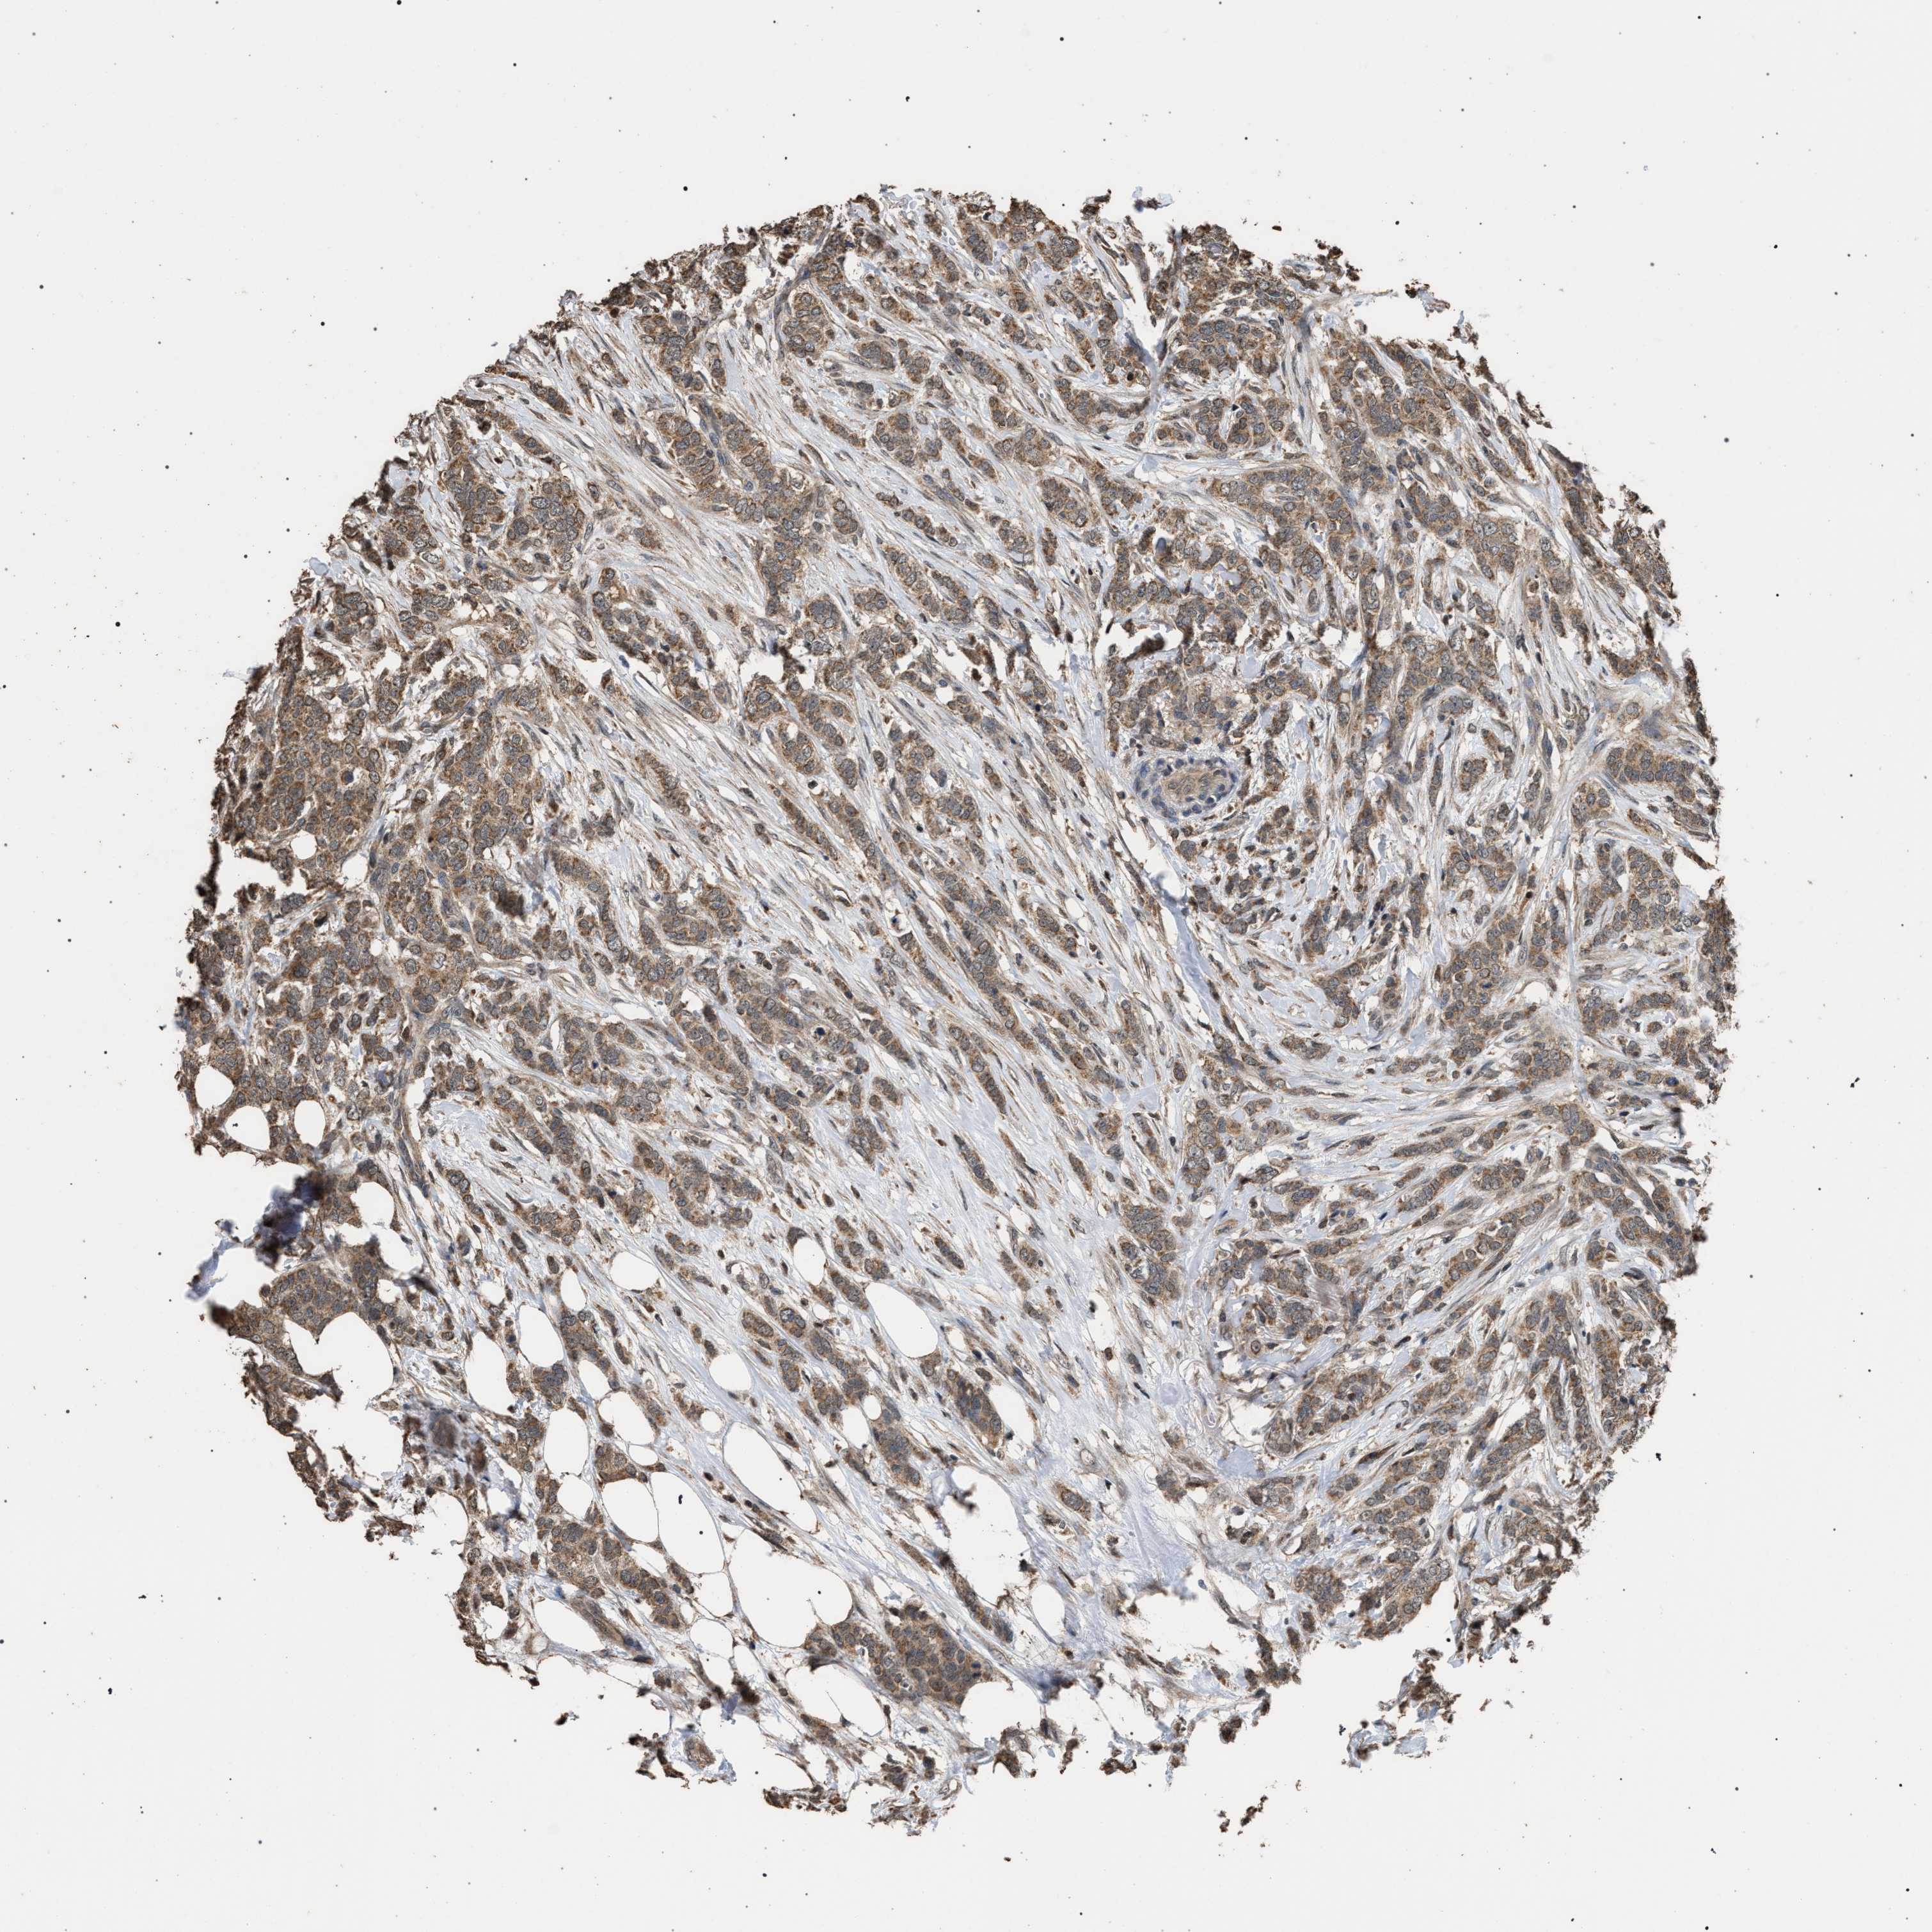

CANCER BREAST CANCER Show tissue menu

BRCA TCGA BRCA VALIDATION PROTEIN EXPRESSION